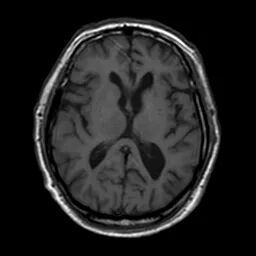

颅脑磁共振+头颈MRA:未见新发梗死;右侧颈内动脉C1段重度狭窄。

什么叫桡鞘【例久弥新】寻道于桡——瑞康通5.5F Introsky X导管鞘经桡入路治疗颈动脉重度狭窄一例_https://www.jmylbn.com_新闻资讯_第6张